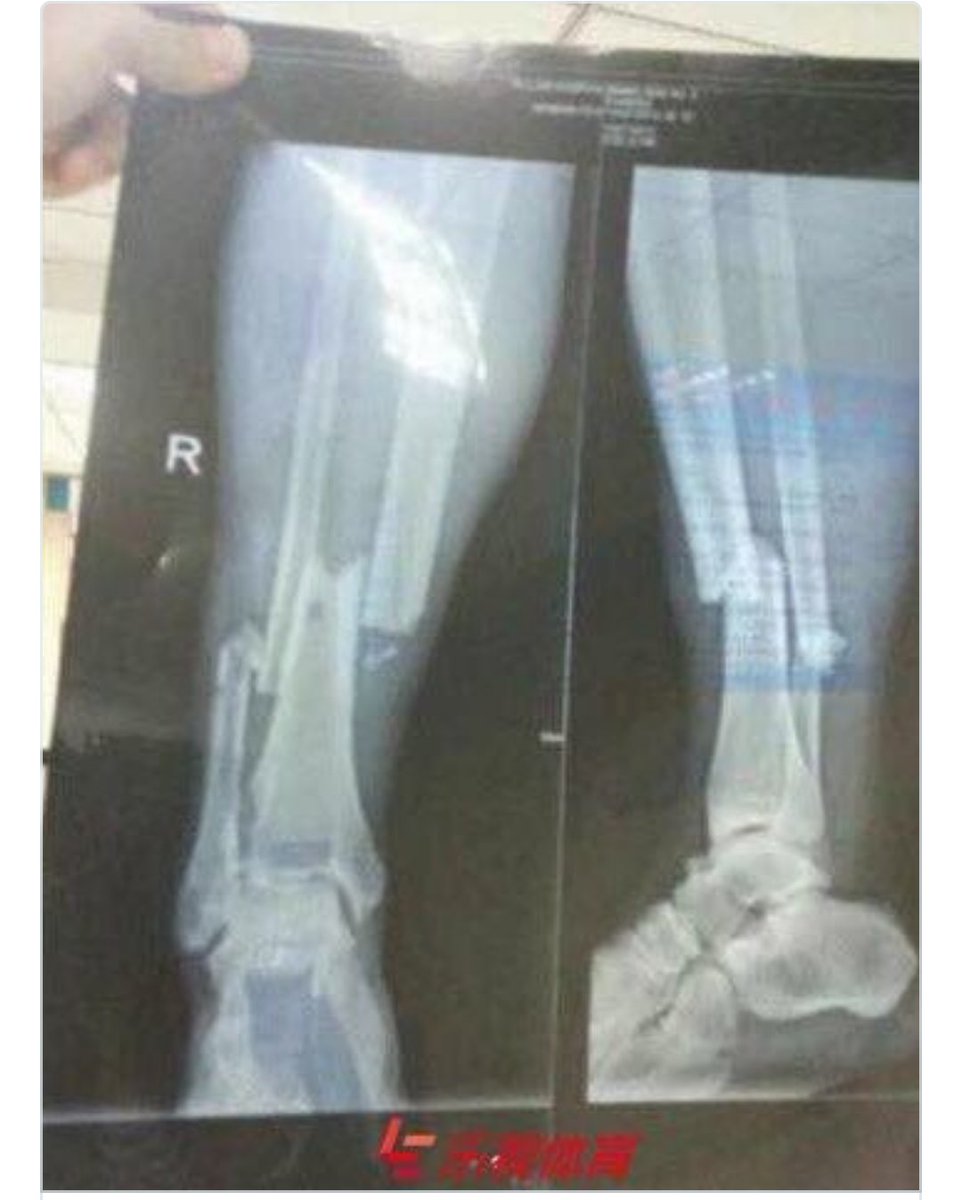

Title : Horor Inilah Hasil X Ray Patahan Kaki Demba Ba Bola Net Source : www.bola.net Open New Window

Title : Inilah Hasil X Ray Cedera Horor Demba Ba Goal Com Source : www.goal.com Open New Window

Title : Foto Mengerikan Ini Hasil X Ray Dari Patah Tulang Demba Ba Indosport Source : www.indosport.com Open New Window